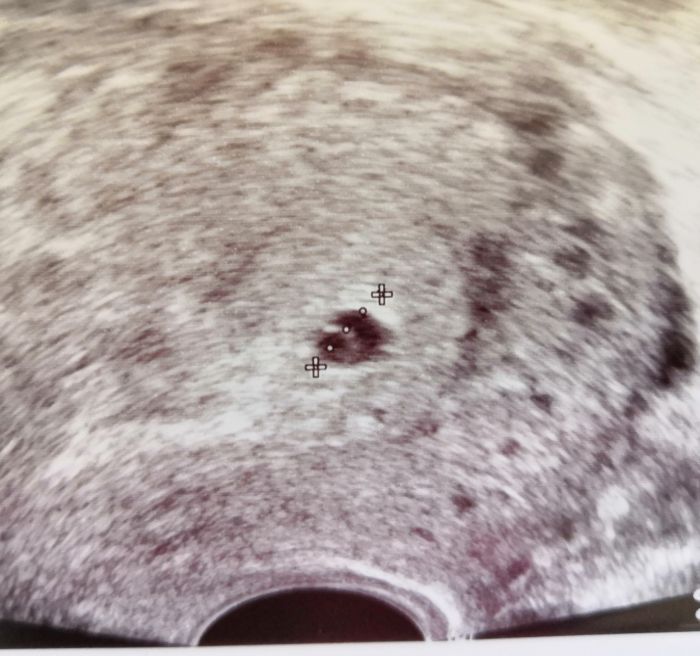

Takový bobeček :-*

Theo nádherná fazolka, gratuluji

Juu, Theo krásná fazolka

Theo, moc gratuluji, krásná fotečka!

Theo, paradni fotka, moc gratuluju!